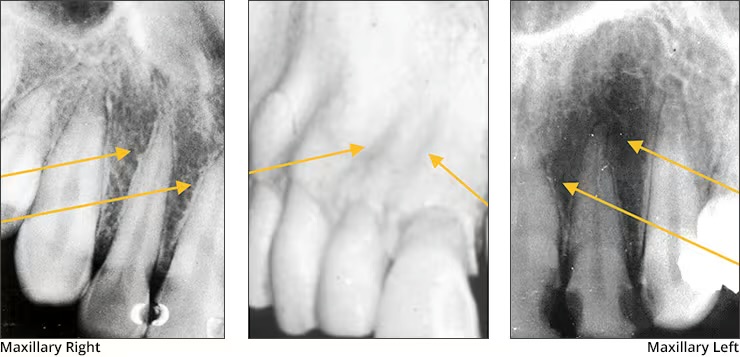

Walls of sinus

Appears radiopaque

Sinus cavity

Appears radiolucent

Nasal fossae

Appears radiolucent. Seen on maxillary central incision PA’s and somewhat on lateral incisor and canine PA’s

Median palatine suture

Appears as a thin vertical line in the midline on max central incisor PA’s

Is where the two halves of the maxillary come together

Anterior Nasal Spine

Appears “V-shaped” or “triangular point”

Is a bony projection located at the base of the nasal septum in the maxillary midline